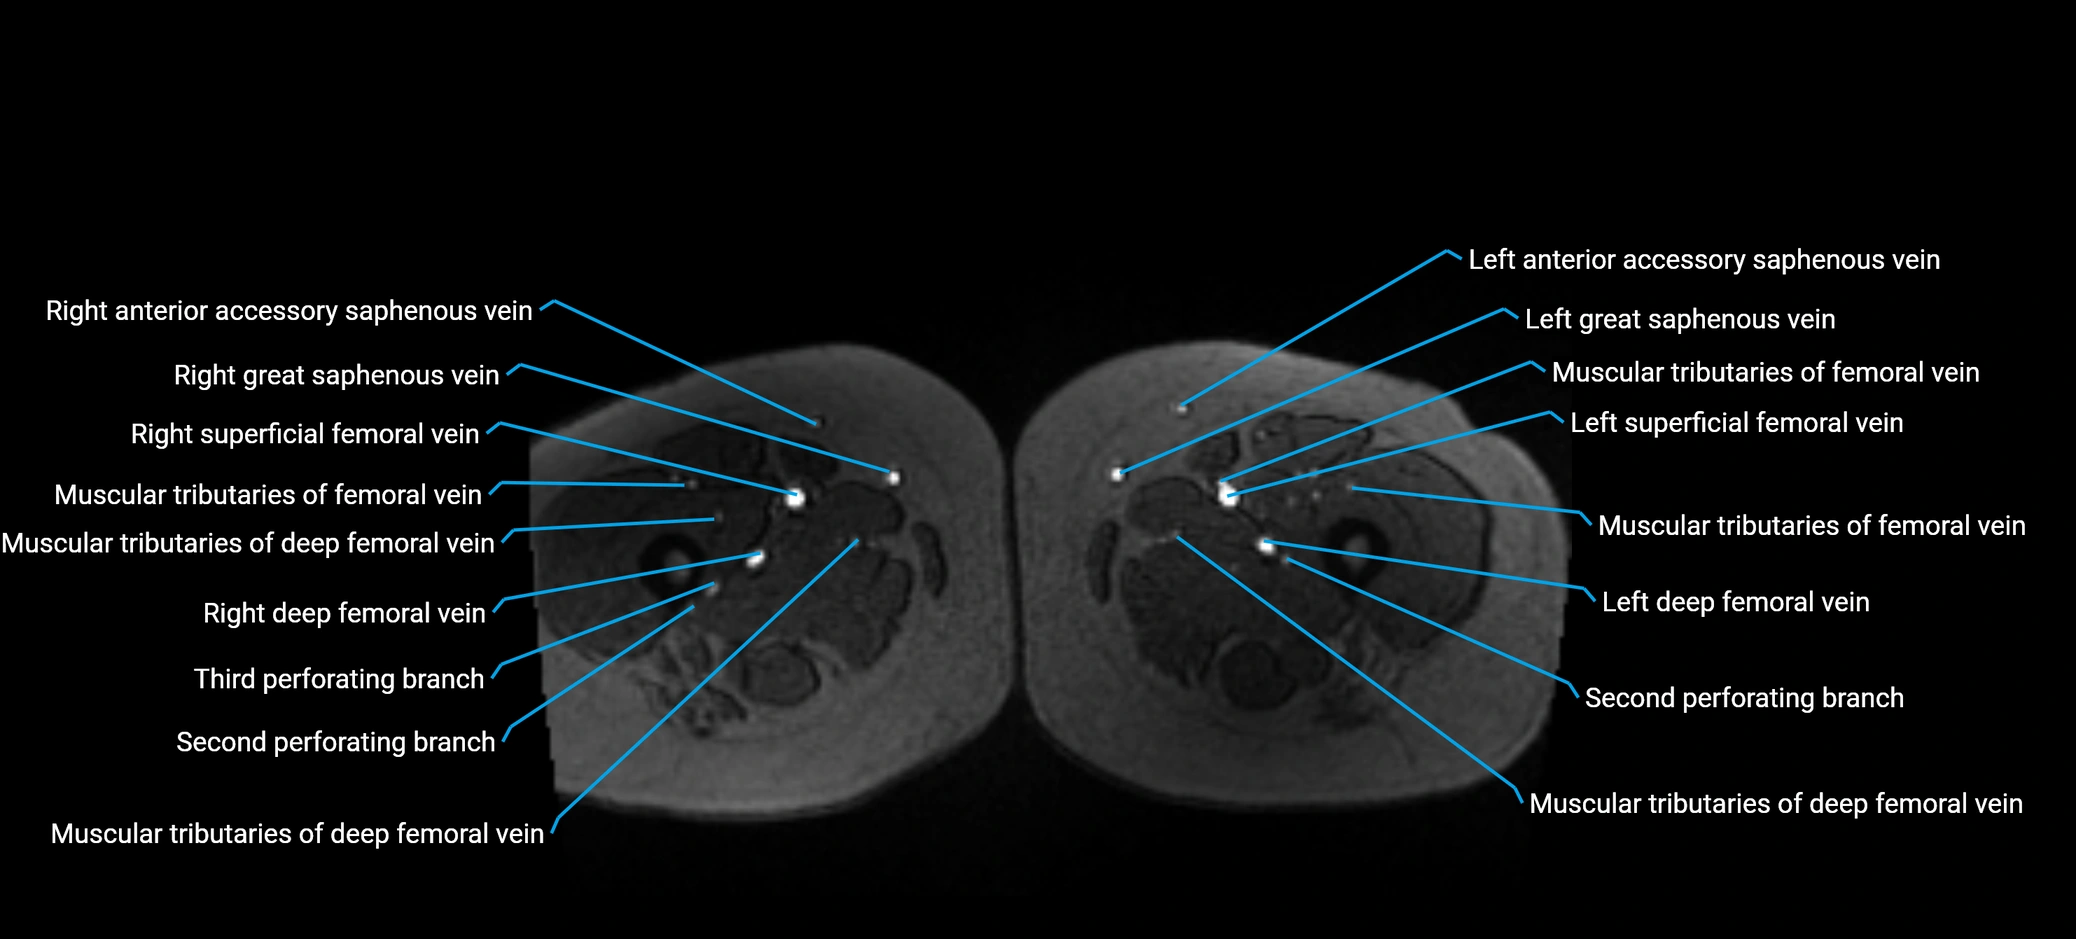

MRI image

image